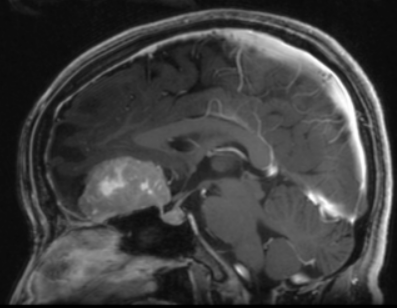

מחצית מגידולי ההיפופיזה, אינם מפרישים הורמוני (non-functioning) והתסמינים נגרמים בשל הלחץ של הגידול שגדל על מבנים הסמוכים, ועלול לגרום להפרעות בראייה עד לכדי עיוורון והפרעה בהפרשת ההורמונים. גידולים קטנים מהסוג הלא מפריש, לרוב אינם מצריכים טיפול, אלא מעקב מרפאתי ע"י ביצוע MRI מוח תקופתי. גידולים לא מפרישים גדולים או גידולים המפרישים (secreting tumors), מצריכים טיפול. קו הטיפול היעיל הראשון הוא ניתוח אשר לרוב מבוצע דרך האף בגישה טרנס-ספנואידלית אנדוסקופית (ראה סרט). בניתוחים טרנס-ספנואידלים אנדוסקופים מורכבים, הצוות הרפואי כולל: נוירוכירורג ורופא אא"ג. דרך פתח נחיר האף, יוצרים המנתחים מסדרון דרכו ניתן להגיע לאזור הגידול ולכרות אותו וזאת מבלי לפתוח את הגולגולת או לעבור דרך רקמת מוח. בטיפול בחולים עם

גידולי היפופיזה, משתתף צוות רב-תחומי הכולל נוירוכירורגים, רופאי אא"ג, אנדוקרינולוגים ורופאי קרינה, המקיימים ישיבות שבועיות לצורך דיון מולטידיסיפלינארי והחלטה על אופן הטיפול המיטבי לחולים.